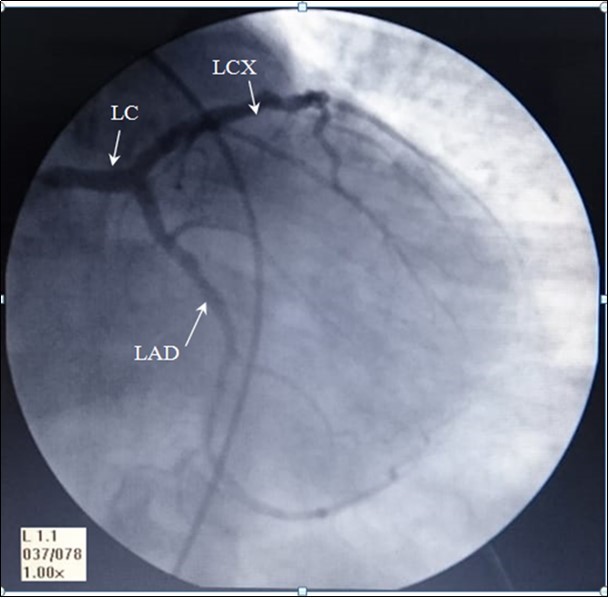

The angiography of these arteries is illustrated in Figure 1.

Figure 1.AP- anteroposterior angiographic view showing, Left coronary artery: LC, left anterior interventricular ( anterior descending) artery: LAD, and Left Circumflex artery: LCX

AP- anteroposterior angiographic view showing, Left coronary artery: LC, left anterior interventricular ( anterior            descending) artery: LAD, and Left Circumflex artery: LCX